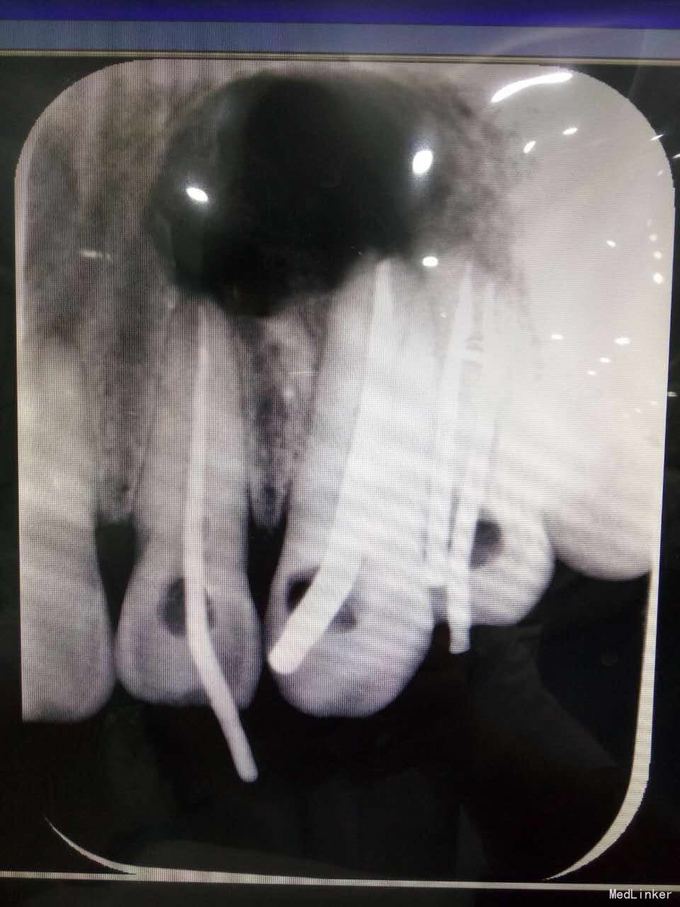

24牙合面龋坏,龋坏较深,未穿髓,龈红,无窦道,无松动 23牙牙体完整无明显松动 22牙牙体完整,腭侧有窦道,无明显松动 X线示23牙根尖牙周组织可见1cmX10cm囊肿,波及22牙及24牙

22牙牙髓部分坏死 23根尖囊肿 24牙髓坏死 1.22牙23牙24牙RCT 2.转外科行23牙囊肿摘除术 23牙MTA根尖封闭,拍片,确定根尖封闭良好,使用热牙胶垂直加压充填,流动树脂垫底,Z350树脂充填抛光 22牙24牙根充,流动树脂垫底,Z350充填抛光